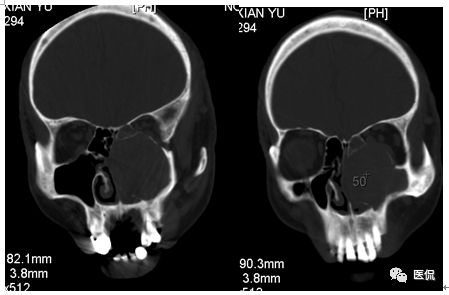

增强静脉期

CT平扫及增强示:左侧上颌窦及鼻腔可见软组织密度影,呈膨胀性生长,周围骨质压迫性吸收破坏,累及左眶,病灶密度不均匀,周边区可见点状钙化,增动脉期轻度强化,局部见小灶性稍高密度区,静脉期病灶内见不均匀明显强化,CT值最高达117HU,延迟期强化范围有所增大。

影像学表现呈软组织密度,多不均匀,表现为高低混杂密度,病变窦腔内息肉、血肿、坏死、感染共存,是病灶密度不均匀的主要原因,息肉反复出血、血管机化亦为其成因之一。病灶内钙化,可为团块状或小片状,可能为病变组织坏死后钙质沉着所致。由于病变组织内有大量炎性细胞浸润和丰富的毛细血管,增强后常有强化。有文献报道病灶增强中心区强化不明显,外周呈轻度强化,推测病灶内虽然血管丰富,但中心区容易出现血流动力学障碍,血管内常有血栓形成,中心区易发生出血坏死,另外,可能与增强扫描延迟时间选择不当有关。

本例病灶较大,周围骨质可见吸收破坏,并累及眼眶,病灶内少量钙化,增强扫描具有一定特征性,表现为动脉期轻度强化,局部见小灶性稍高密度区,静脉期病灶局部呈明显强化,CT值最高达117HU,延迟期强化范围有所增大,呈延迟渐进性强化的特点,推测为病灶内出血所致。